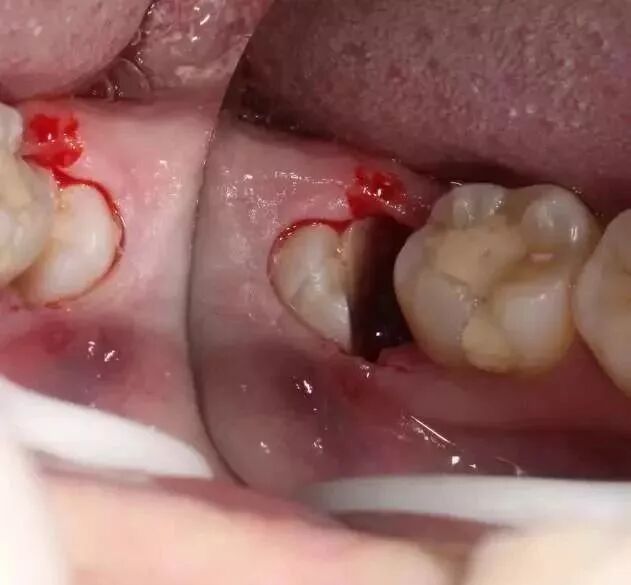

拔牙操作

拔牙,这两个字是无数的技巧、经验、医学原则的体现,恕我无法展开,也不知道怎么写出来才能让大家理解。举个例子:

一颗横生的智齿,钳子是搞不出来的。我可以拿出锤凿把它劈开搞出来,也可以拿出涡轮机把它磨开搞出来,对患者带去的影响是一样的吗?前者会造成患者心理恐慌,加重关节负荷,后者会带来更高的术后感染、局部反应风险。

由于智齿的生长位置特殊,导致了拔除难易不同,如智齿出现横着长或者靠近牙神经的话,则难度会较高,一般人只需拍个口腔全景片,但相对于智齿靠近神经管的情况,还可能需要拍CT,这都很考验牙医的技术。

各种方法各有优缺点,关键在于牙医的技术把握和对风险的控制能力。